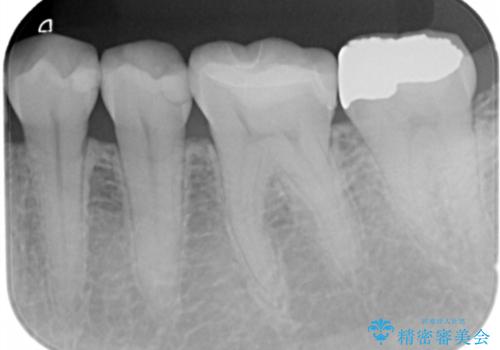

- 歯が黒くて虫歯じゃないかと心配して来院。

過去にプラスチックの樹脂で治療されており、歯とプラスチックの隙間から虫歯が進行していました。

拡大鏡下で虫歯を除去し、詰め物にて治療しました。

一番奥の歯は歯の高さが足りない、噛む面を覆う面が広くなってしまい、セラミックの詰め物だと割れるリスクが高くなってしまうので手前はセラミックインレー奥の歯はゴールドインレーにて治療しました。